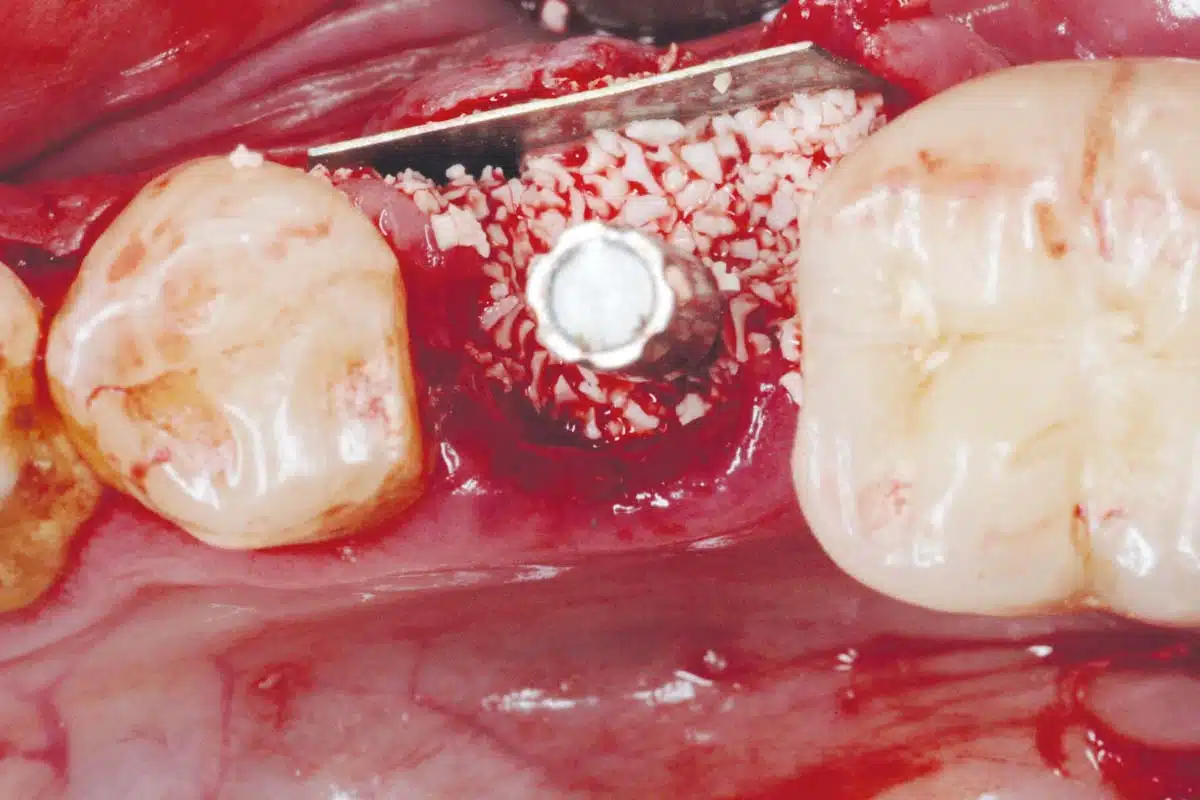

PR Elie Maalouf, Dr Fady Abillamaa, Dr Cynthia Chemaly and Dr Alain Abi Sleiman

cerabone®NOVAMag® membraneNOVAMag® SHIELD